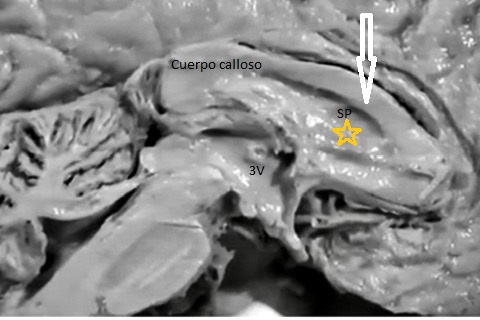

Cuerpo calloso: es una estructura compuesta por haces nerviosos cuya función es la de conectar e integrar regiones corticales homólogas entre ambos hemisferios cerebrales. Su ausencia total puede conducir a problemas cognitivos y del desorrollo psicomotriz o pasar totalmente desapercibida. Su ausencia parcial, paradójicamente, se asocia con peor pronóstico. Como estructura ecográfica, es una de las más bellas que hay en el cerebro pero, para obtenerla se requiere pericia y muy buena resolución ecográfica. Sus alteraciones congénitas son diagnóstico de problemas primarios del desarrollo cerebral y se manifiestan con cambios indirectos en otras secciones cerebrales, especialmente ventriculomegalia.